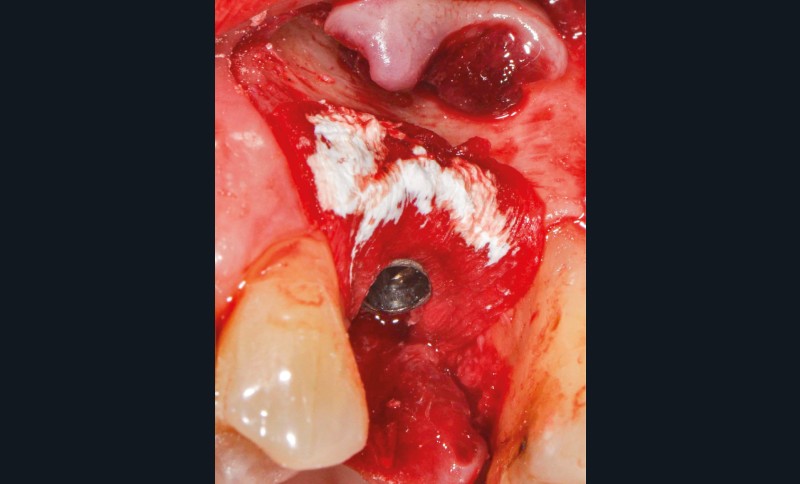

Chez cette patiente, le traitement de la péri-implantite a été réalisé à l’aide d’une technique de régénération osseuse guidée péri-implantaire, dont l’indication a été principalement motivée par la morphologie du défaut osseux. Au-delà de la maîtrise du geste chirurgical, le bon résultat obtenu à trois ans est intimement lié à sa coopération en termes de suivi et de contrôle de plaque.

13 et 14. À 3 ans, une régénération osseuse satisfaisante et un bel aspect des tissus péri-implantaires sont observés. Les poches font 3 mm en mésial, distal et palatin, et 2 mm en vestibulaire. Il n’y a pas de saignement au sondage.